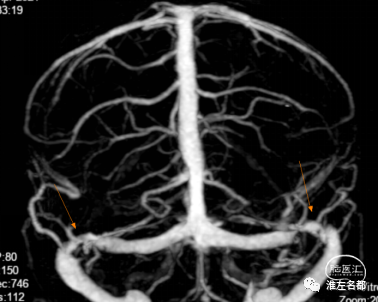

增强MRV示:左侧横窦、乙状窦和颈内静脉显影不清,右侧横窦粗大,近端管腔严重狭窄(橙箭)。

CTV示:双侧横窦局部管腔严重狭窄(橙箭)。